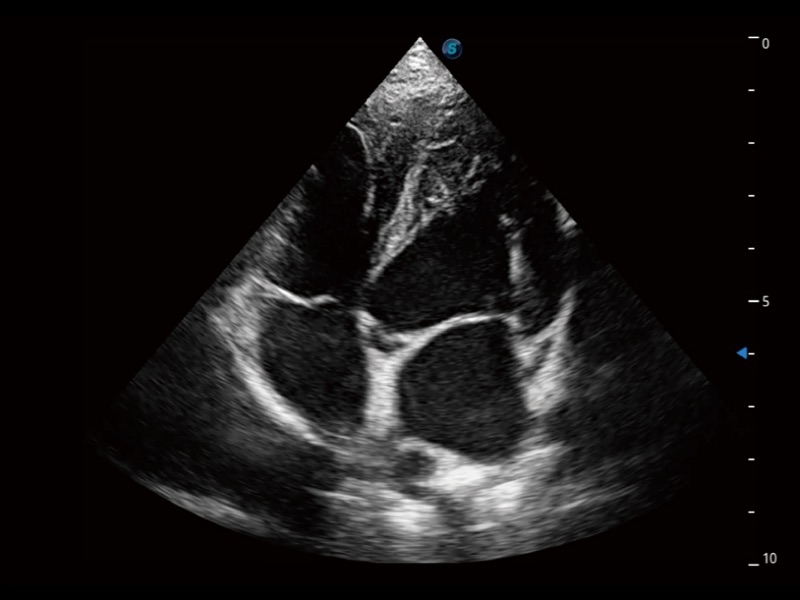

大型犬、马科、农场动物及大型异宠动物

通过360度任意调节3条M型取样线,在同一心动周期上观察心脏不同位置的运动曲线,得到准确的心功能测量数据,有效评估心肌运动及左心室功能。

实时用颜色表示心肌组织运动,观察和定量组织的运动情况,对快速检测与评估心肌的灌注和活性、电传导及心肌收缩和舒张功能等均能提供重要的诊断信息。

ProPet 70专为动物医生设计,对不同的动物体型和生理结构作出了针对性的优化。通过动物影像专用软件,可满足个性化的应用需求,帮助动物医生获得更精确的诊断数据。